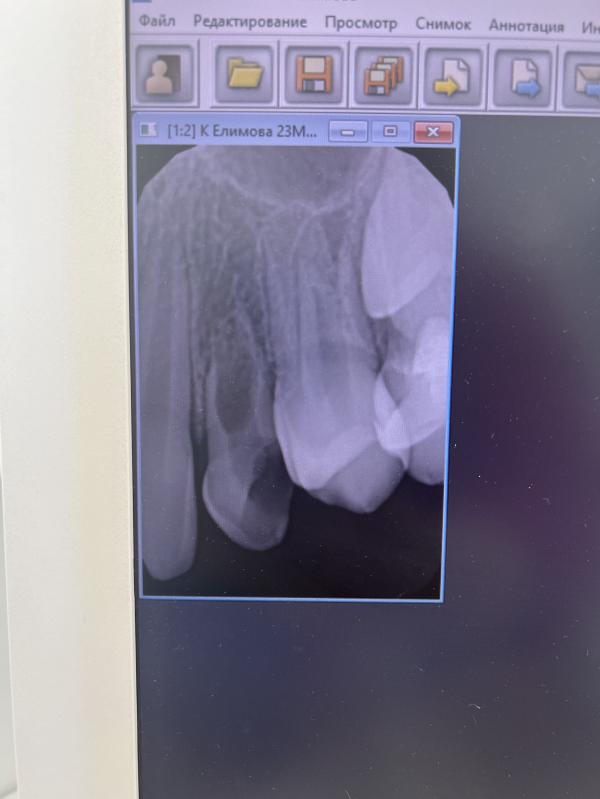

Пока снимок сделали на одном

Сверху, второй сверху тоже не менялся.

Внизу клыки уже поменялись. Думала про еще одну консультацию, но не знаю что это даст 🤔

@vkusnyasha_tonya вообще по одному такому микроснимку не судят. Сходите в президент. Консультация ортодонта бесплатная, снимки там нормальные полноценные делают